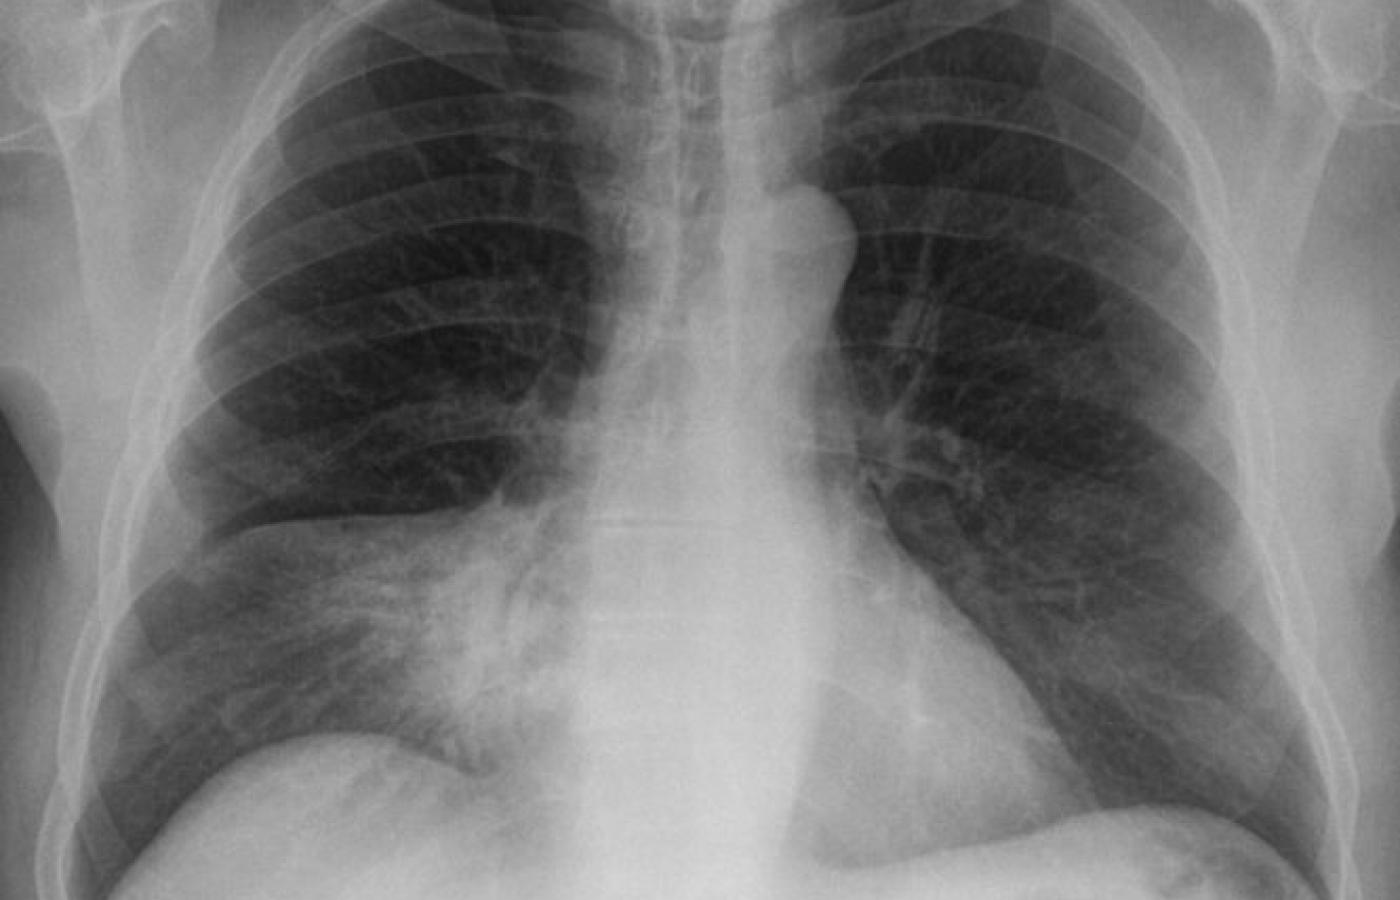

Hellerhoff / Wikipedia

Udało się wyhodować sztuczne płuca, które pracują.

Ponieważ tkanka płucna  właściwie się nie regeneruje, poważne schorzenia płuc są niezwykle trudno wyleczalne i najczęściej jedynym lekarstwem jest transplantacja. Z tym jednak, jak z innymi organami do przeszczepu, zawsze jest problem z racji niedostępności dawców. Naukowcy postanowili więc wyhodować tkankę płucą in vitro, a nastepnie tak zregenerowane płuca wszczepić pacjentowi. Na razie szczurowi. Udało sie to na Uniwersytecie Yale, o czym donosi najnowsze (25.06.2010) wydanie czasopisma Science. Najpierw z pobranych szczurzych płuc wycięto istniejący komponent komórkowy, pozostawiając jednak główną strukturę organu, a więc naczynia krwionośne oraz kanały, którymi powietrze jest w płucach transportowane. Powstało coś w rodzaju bezkomórkowego łożyska płucnego, które następnie umieszczono w specjalnym bioreaktorze, symulujacym warunki, w których płuca rosną w płodzie. Po wielu dniach hodowli udało się wytworzyć brakujące komórki, a gdy następnie szczurowi wszczepiono - na dwie godziny - tak bioinżynieryjnie zmodyfikowany organ, zaczął on prawidłowo pracować. Nowe płuca dokonywały przemiany tlenu i dwutlenku węgla oraz natleniania hemoglobiny we krwi. To pierwszy istotny krok. Potrzeba jednak jeszcze wielu dlaszych badań, by zdobyć  pewność, że  ta procedura będzie skuteczna na dłuższą metę i że będzie można zastosować ją u ludzi.